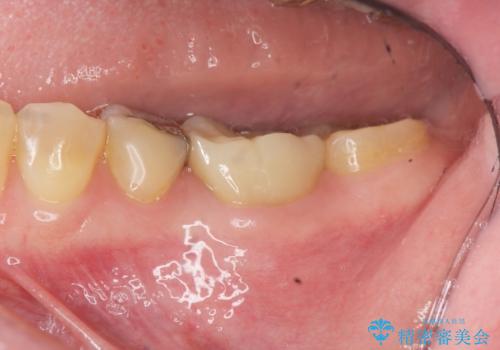

放置された虫歯 小矯正+歯周外科による保存処置